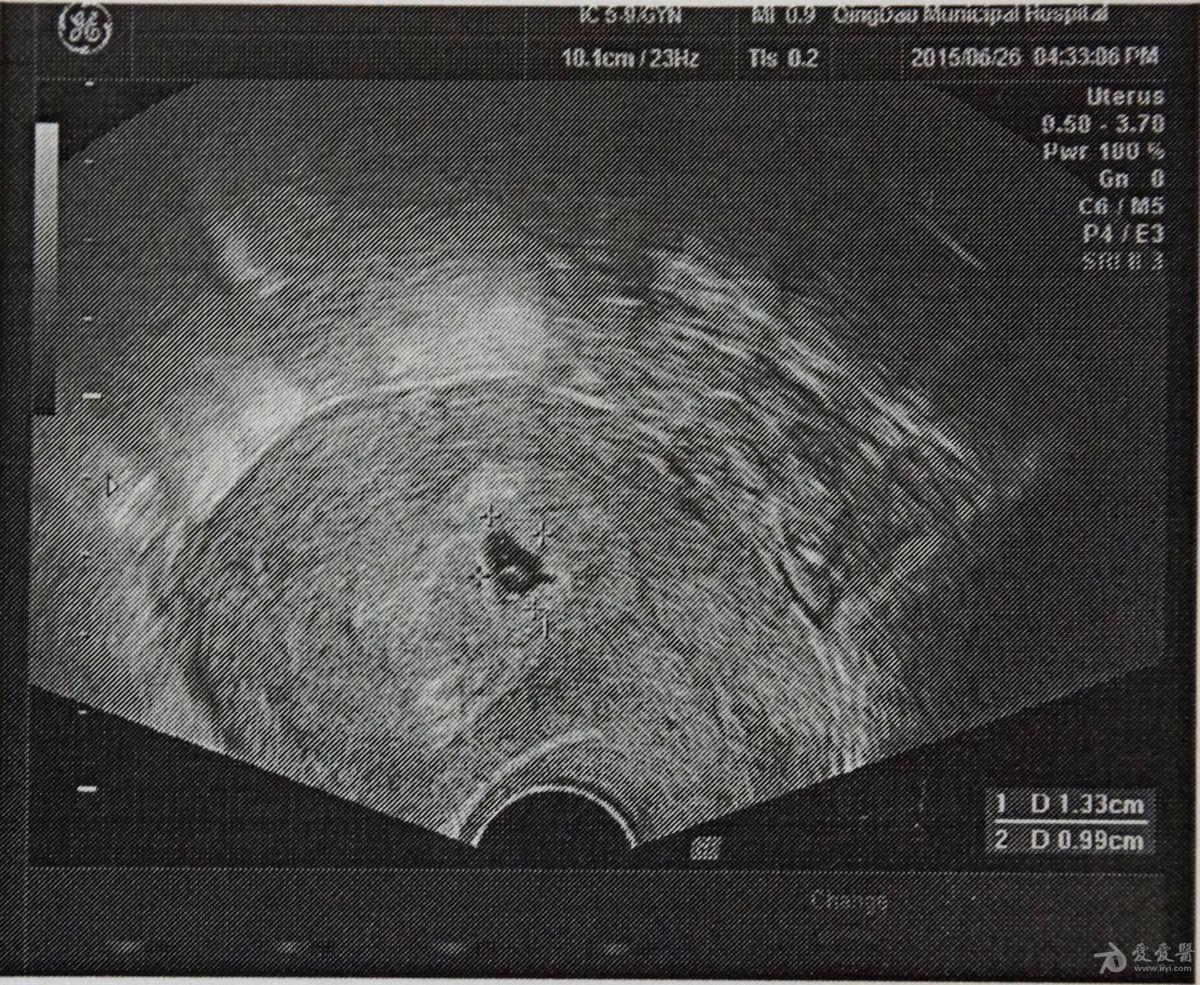

目前怀孕六周,因**有褐色分泌物,于是去医院检查,医生怀疑孕酮低,但是验血后,孕酮值和β-HCG值都正常。医生说孕囊变形。请各位帮忙看下,孕囊变形是否严重,还有补救的希望吗?目前应该采取什么措施?拜谢!!!

正常孕囊应当圆形或者椭圆形,这b超中已经是不规则变形了,说明发育异常。再加上有**流血,所以要考虑终止妊娠的准备。

感谢各位的热心回答,今天去医院又做了检查,新拍了一张B超,我感觉形状还不是那种规则的圆形或椭圆形。还得麻烦各位给看一下,形状是否正常呢?现在有了胎心和胚芽,但还是有出血现象。